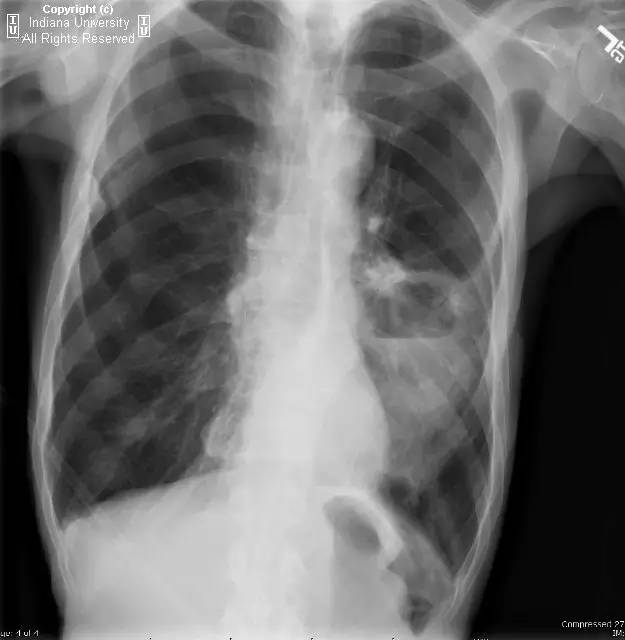

【病史】男性,咳嗽,体重减轻。

胸片示肺内高度膨胀性病变,膈肌扁平。左后胸部可见较大卵圆形不透亮区并液平面。CT示左肺下叶近后胸壁较大厚壁肿块并部分空洞形成,实性部分不均质强化。右肺下叶可见分叶状结节。左前下少量气胸。

【诊断】鳞状细胞肺癌并后部阻塞性肺炎